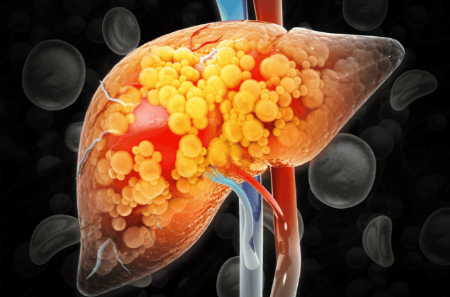

چرا قند اضافی قاتل خاموش است؟

از میان سه تهدید اصلی کبد (الکل، قند اضافی و چاقی)، قند اغلب مخفیترین آنهاست. بدن قند را به گلوکز تبدیل میکند؛ اگر فوراً مصرف نشود ابتدا به صورت گلیکوژن در کبد و عضلات ذخیره میشود. اما فضای ذخیره محدود است! گلوکز اضافی به چربی تبدیل میشود – بهخصوص در کبد. اینجا مشکلات شروع میشود: کبد چرب، کلسترول بالا، گرفتگی عروق و افزایش خطر بیماریهای قلبی و مغزی. با کاهش مصرف قند نه تنها فشار را از روی کبد برمیدارید، بلکه چشمها و کل بدنتان سالمتر میمانند.